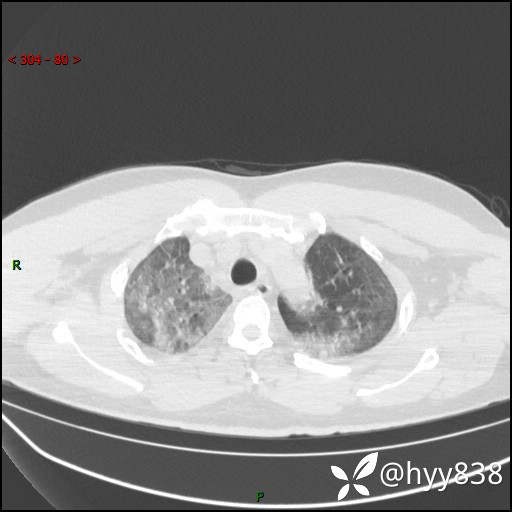

辅助检查:CT

临床诊断:间质性肺炎

第二次CT(7天后)